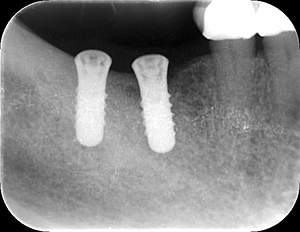

レントゲン写真

- 透過像

| 年齢 | 50代・男性 |

| 主訴 | 右下歯が疼く |

| 治療内容 | ・右下6番インプラント ※1:FGG(遊離歯肉移植術)とは、足りない歯ぐきを上顎から上皮を切り取り移植する外科手術 |

| 治療費 | 合計:902,000円(税込) ■内訳 |

| 治療期間 | 9ヵ月 |

| 治療方針 | 右下の当該歯は歯根破折により保存不可能と診断しました。歯周疾患も伴っていたため抜歯後に骨吸収※1が大きく起こることが予測できました。チタンメッシュ併用骨再生誘導法(GBR※2)を選択しインプラント埋入と同時に行い自然な歯槽骨のラインを再現しました。またGBRを行う際にインプラント辺縁の付着歯肉の減少が起こる為、遊離歯肉移植術(FGG※3)を行い清掃性を考慮した形態に仕上げました。 ■治療方針の解説 治療した右下の歯をレントゲンで撮影したところ根本の部分に黒く写る箇所があり「根尖性慢性周囲炎※1」と診断。また歯周病も進行していました。 ※1 骨吸収・・・歯槽骨という歯を支える骨がなくなっていくこと |

| 担当者所見 | 主訴の右下だけでなく歯茎の腫れ、発赤があり不良補綴や不良充填など他にも治療箇所が多数ありました。プラークコントロールが不良であった為まずはブラッシング指導を行いセルフケアの重要性を理解していただくところからスタートしました。 右下6番の歯はインプラント治療を行なった結果審美的にも機能的にも患者様の満足を得ることができました。骨造成と歯肉移植も行なった為インプラントを支える十分な歯周組織の獲得ができたと思っております。 |